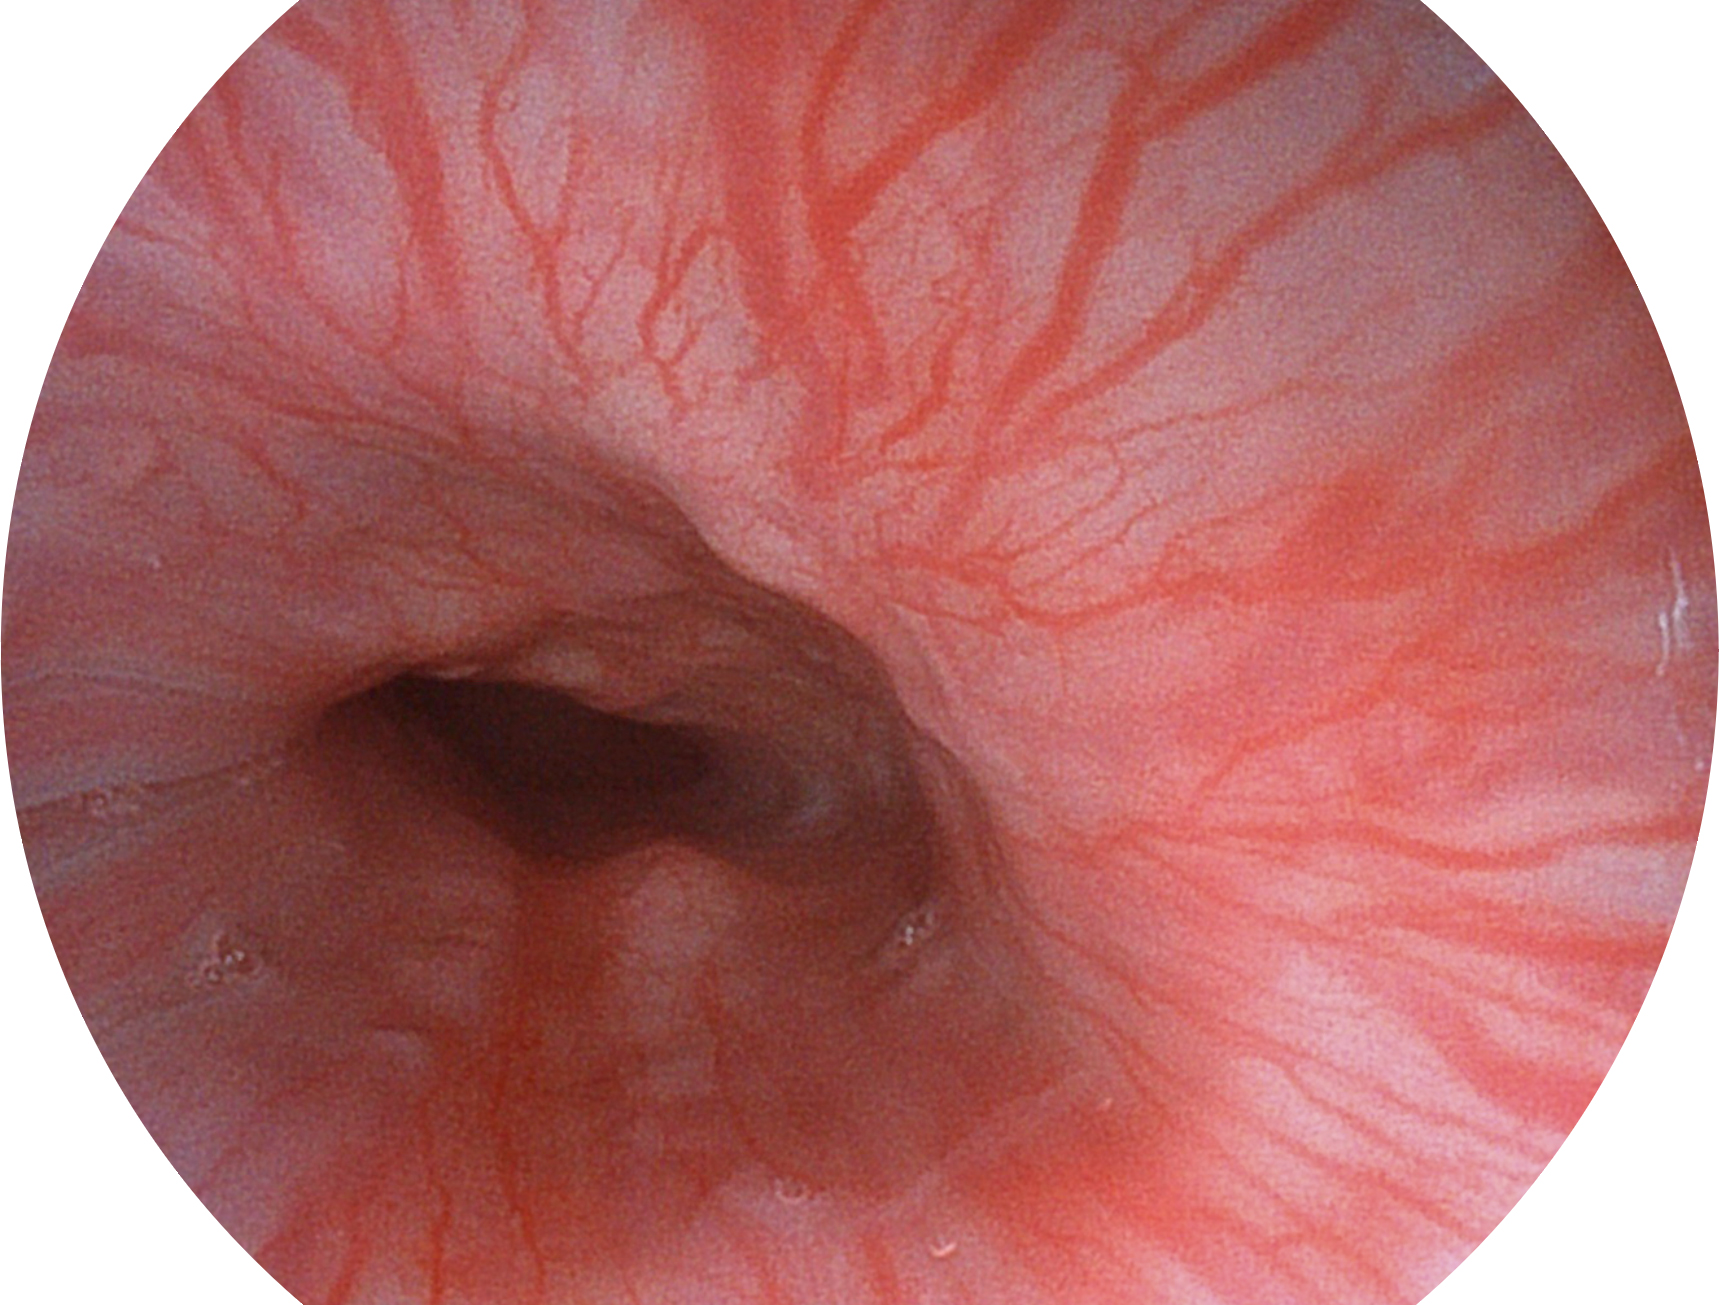

开立新开发的内镜染色技术,主要是基于多波长LED 光源的开发,VLS-55Q 四波长LED 光源是由四个不同颜色的LED光按照相应照明模式所规定的特定发光比例进行合束后形成,合束后形成的照明光的光谱由红光、绿光、蓝光及蓝紫光这四个不同的波段范围构成。具有更高光谱自由度,通过光谱比例的控制,实现了聚谱成像技术,英文全称为“Spectral Focused Imaging, SFI”,缩写为“SFI”和光电复合染色成像技术,英文全称为“Versatile Intelligent Staining Technology, VIST”,缩写为“VIST”。